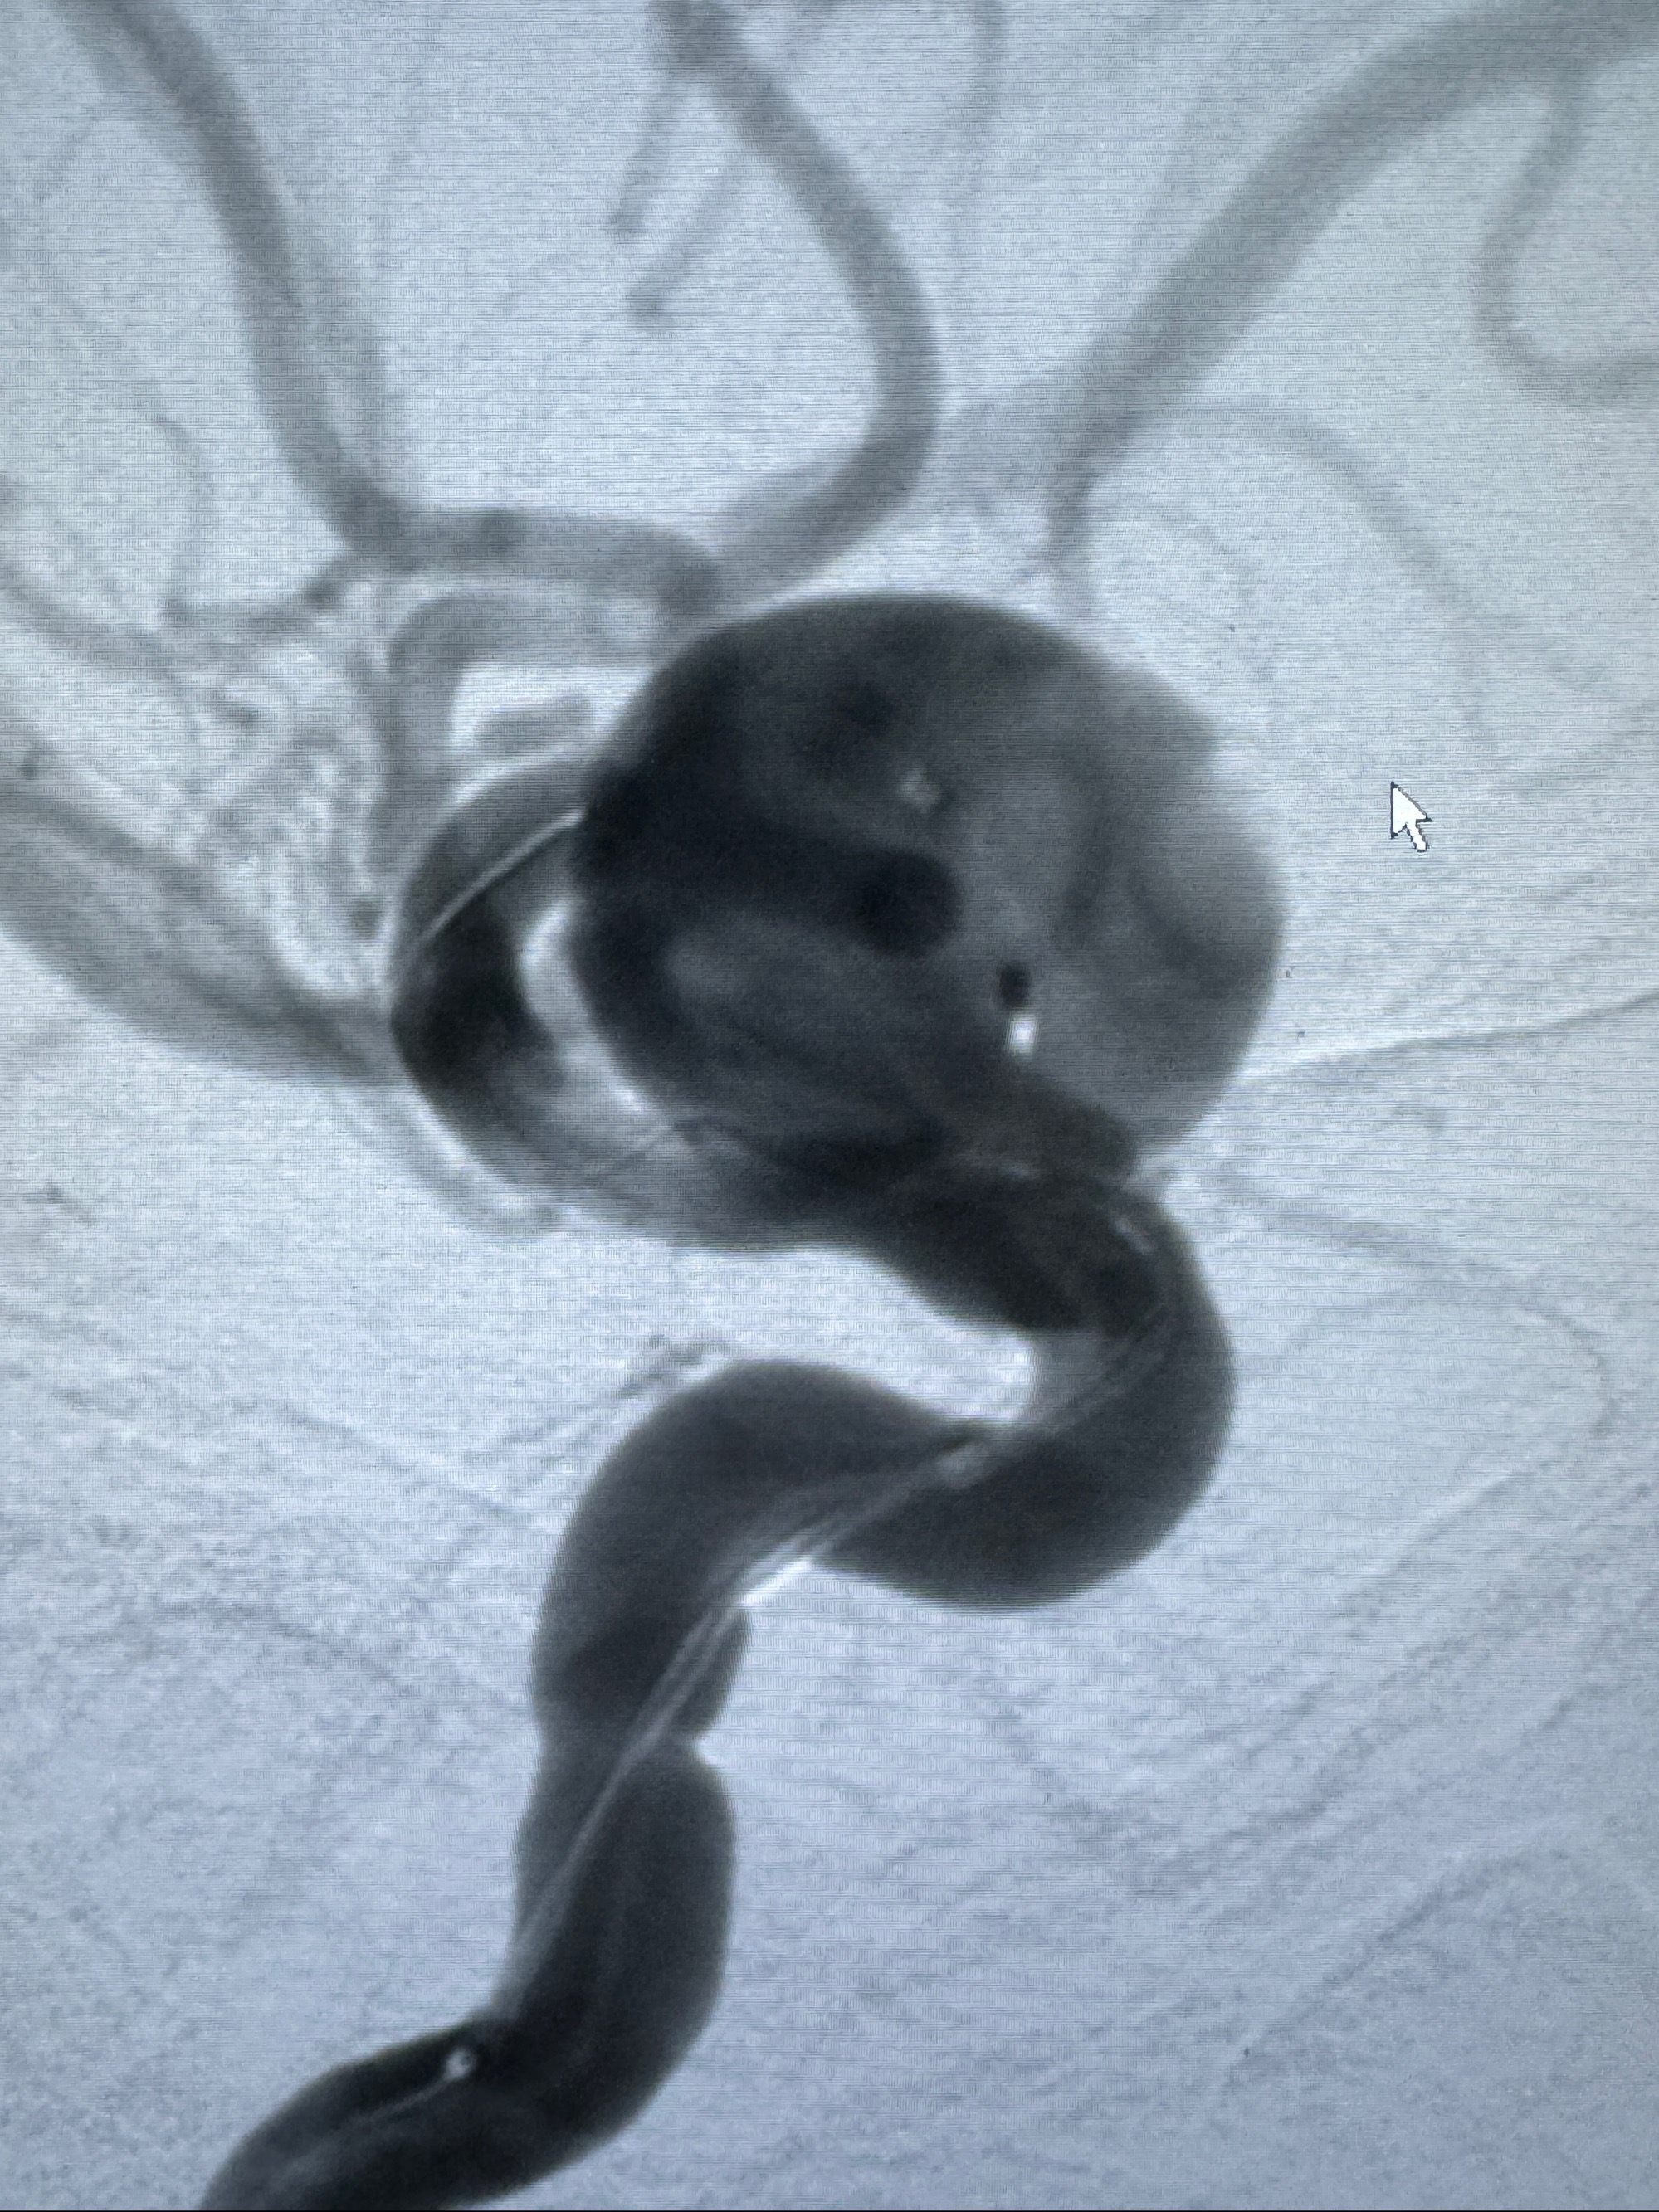

2023-12-08外院DSA:右侧颈眼动脉瘤,约13*12mm大小,压颈试验显示左右向及后向前代偿可

旋转3D展示动脉瘤局部的血管构筑

测量动脉瘤的大小:16*13.8*7.6mm大小,较原先变大,考虑双抗后瘤内血栓溶解可能

观察动脉瘤腔内的血流动力学情况